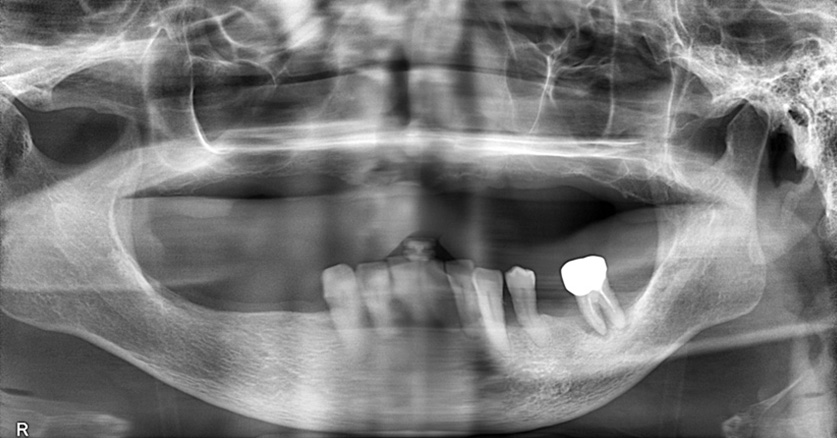

術前のパノラマX線写真

以前、他医院で上下の部分入れ歯を製作したが、下の入れ歯はバネが見えてしまうため使用しなかったとのことでした。

下の前歯部の動揺が大きくなり、抜けてしまうと見た目が良くないため、急ぎで入れ歯を製作したいとのご希望でした。

ご使用中の上の入れ歯もすぐに外れてしまい、上前歯部の見え方もご自身の歯があった時と比べ、見えなくなっていることを気にされていました。

そのため、ご自身の歯があった時のような見え方になるように排列を工夫し、上下の入れ歯を製作することにしました。

動揺の大きい下5本は抜歯し、バネに耐えられそうな3本は保存を試みることにしました。

以前製作した下の部分入れ歯は太いバネ(鋳造のクラスプ)が近心方向からかかっていたため、とても目立っていました。今回は細いバネ(ワイヤークラスプ)にし、遠心から、かつ歯頸部よりに走行させることでバネが目立たない工夫をすることにしました。

抜歯し、5日後には入れ歯をセットすることにしました。